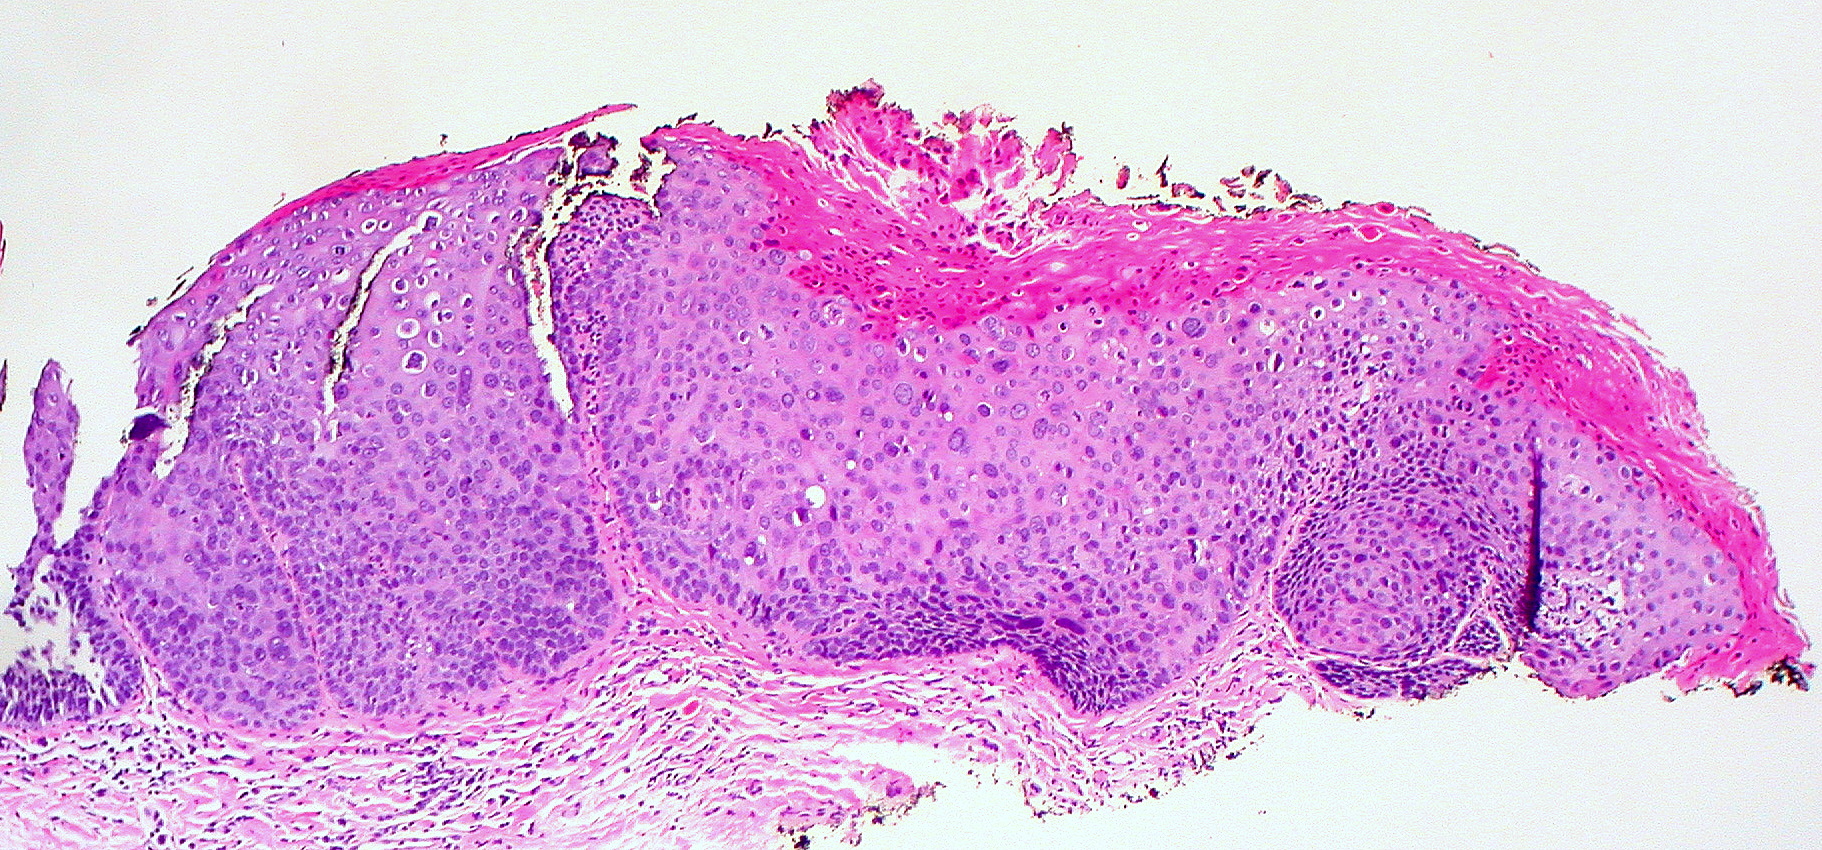

Biopsy is usually not required but the lesion may be excised for cosmetic reasons or due to complications. Histological features of an epidermoid cyst include [1]:

- A cystic structure in the dermis

- A single cavity (unilocular)

- An epithelial lining without rete ridges and with a granular layer with keratinohyaline granules.